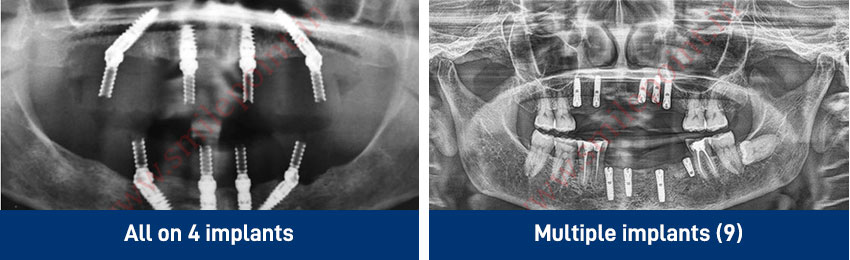

Dental Implants